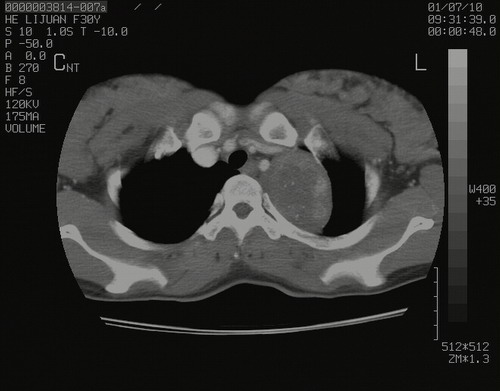

怀孕3个月时(2009-3至4月间),自述突感左侧前后胸疼痛1天,以前胸明显,随后偶感闷痛,余未见异

左肺尖脊柱旁沟肿块,境界清楚,边缘光滑,密度不均,内有多发点片状钙化,考虑良性肿瘤,骨软骨瘤或神经源性肿瘤可能,肺错构瘤不除外。

左后上纵隔见一类圆形肿块影,外侧边界清,密度不均匀,内可见点状钙化影,增强呈不均匀强化,考虑神经源性肿瘤可能。期待病理结果。